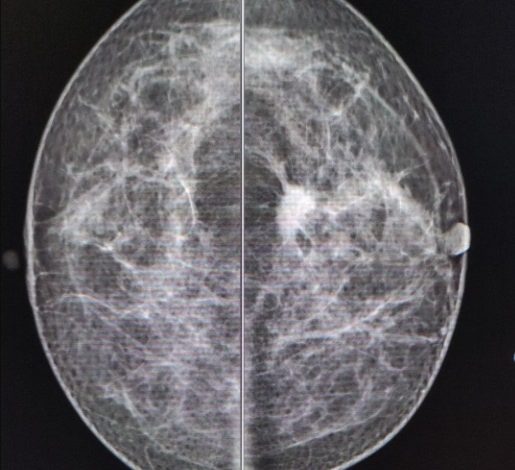

- La mastografía en mujeres entre 40 y 69 años.